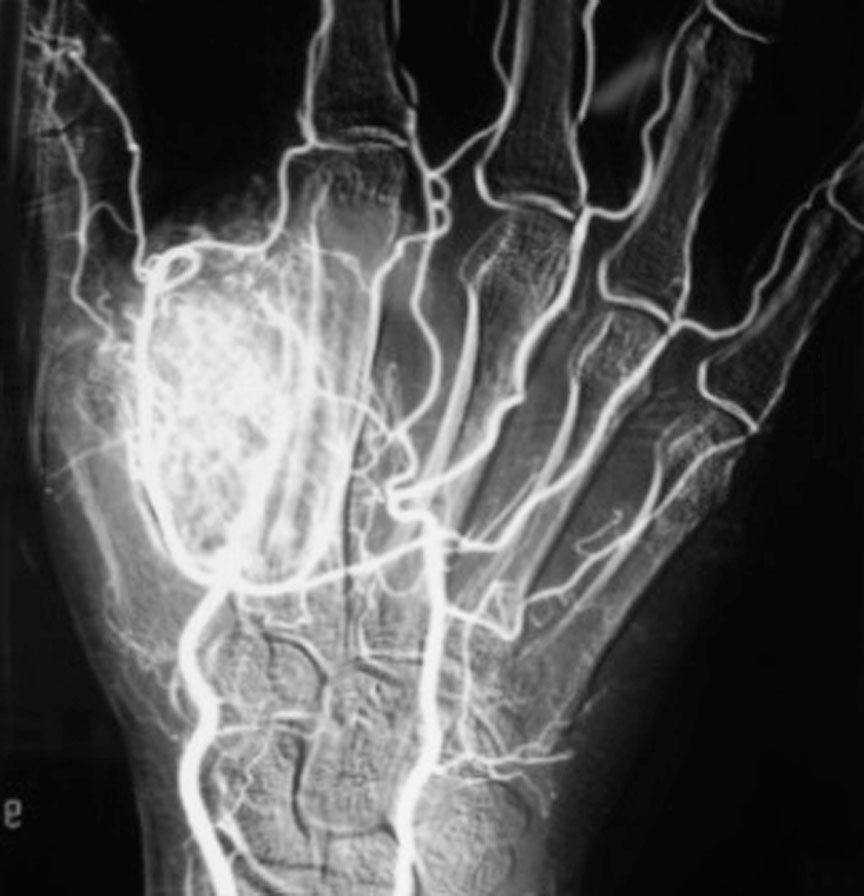

图1-2-32 海绵状血管瘤血管造影

血管造影显示拇指蹼内血管瘤

(2)海绵状血管瘤(图1-2-31、图1-2-32)。